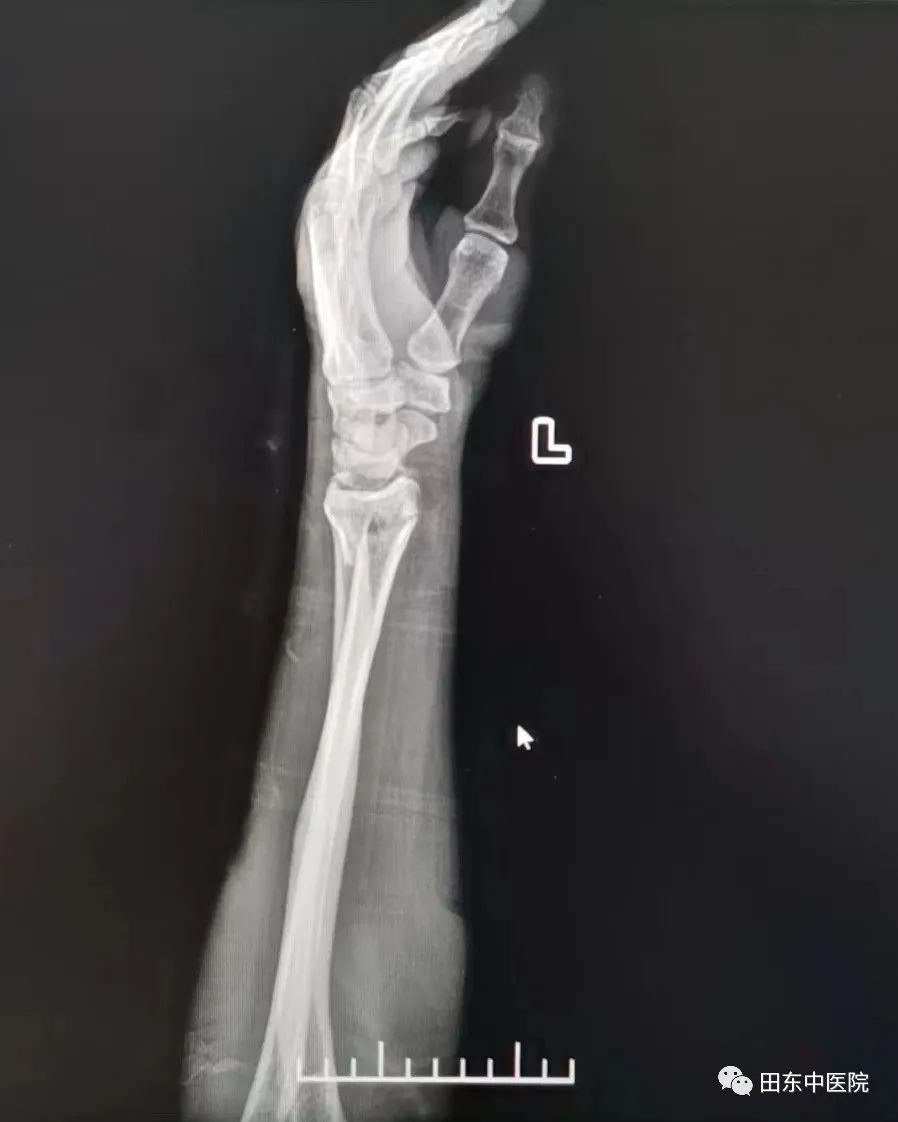

固定后经复查拍片显示:原左侧桡骨远端断端对位线尚可,左腕关节在位。农主任嘱咐患者注意手部皮肤颜色,观察末梢血液循环、感觉及运动情况,指导患者进行握拳伸掌功能锻炼,患肢前臂中立位固定于胸前或放置于身侧。

复位